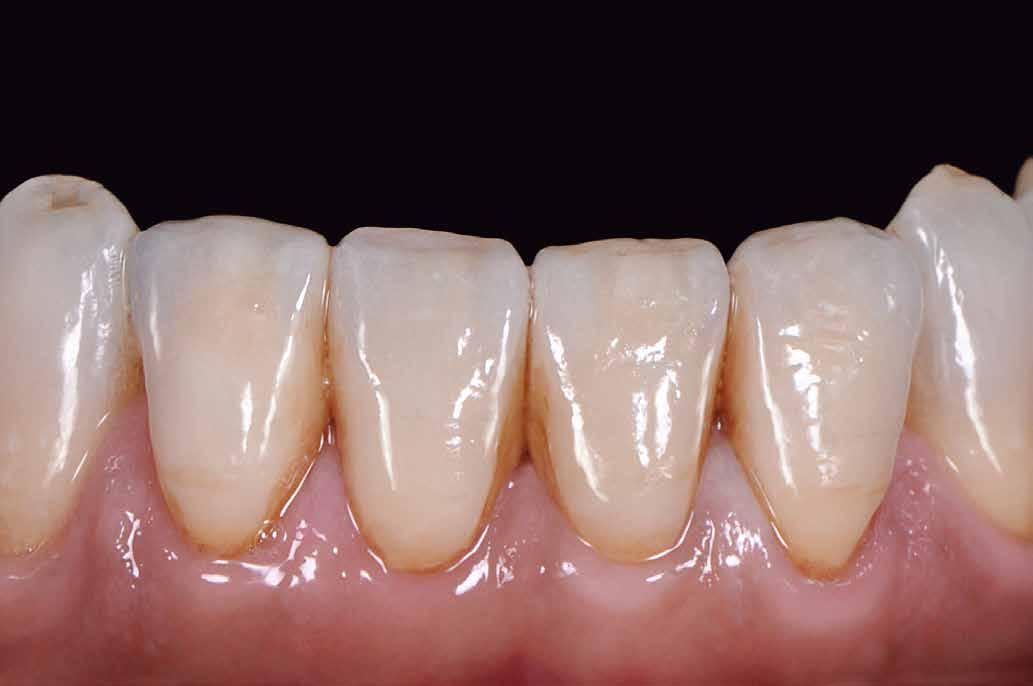

Az oxigén inhibíciós réteg kialakulásának elkerülése érdekében a kerámiafelszíneket glicerin géllel (Liquid Strip, Ivoclar Vivadent, Schaan, Liechtenstein) borítottuk, majd ezeket a felszíneket ismét 20-20 másodpercen keresztül világítottuk. A végeredmény megfelelt a páciens esztétikai igényeinek (6. a. ábra). Az átadott restaurátumok épségének megőrzése érdekében, a páciens számára éjszakai fogvédő sín készült. Az ötéves kontroll alkalmával megállapítottuk, hogy az elvégzett kezelésünk továbbra is sikeresnek tekinthető (6. b. ábra)

Az általunk alkalmazott adhezív rendszerek hatékonyságát nagymértékben növelhetjük azáltal, hogy a fogakat minimál invazív módon, azaz csak zománcon belül preparáljuk, és a kerámia héjakat kofferdám izolálásban ragasztjuk. Jelen esetismertetésünknek az volt a célja, hogy bemutassuk, hogyan lehet az adekvát módon kivitelezett kofferdám izolálással megelőzni

a munkaterület nyállal, vérrel vagy szulkusz-váladékkal történő kontaminációját. A megfelelő méretben kialakított perforációs nyílások és köztük lévő optimális távolság elengedhetetlen ahhoz, hogy a kofferdámot ideális módon tudjuk felhelyezni. Ezzel az esettel azt is bizonyítjuk, hogy a gumilepedő levegőfújással, fogselyemmel és teflonszalagok segítségével történő beforgatásával az ínyvérzés kialakulását el lehet kerülni. Ismételten szeretnénk hangsúlyozni, hogy a megfelelő kofferdám kapcsok használata nélkül nem tudtuk volna a preparált csonkszélt a gumilepedő szélétől eltartani. A kezelés során elért eredményeket jól alátámasztotta, hogy a páciens az ötéves kontroll vizsgálat során teljesen elégedett volt.